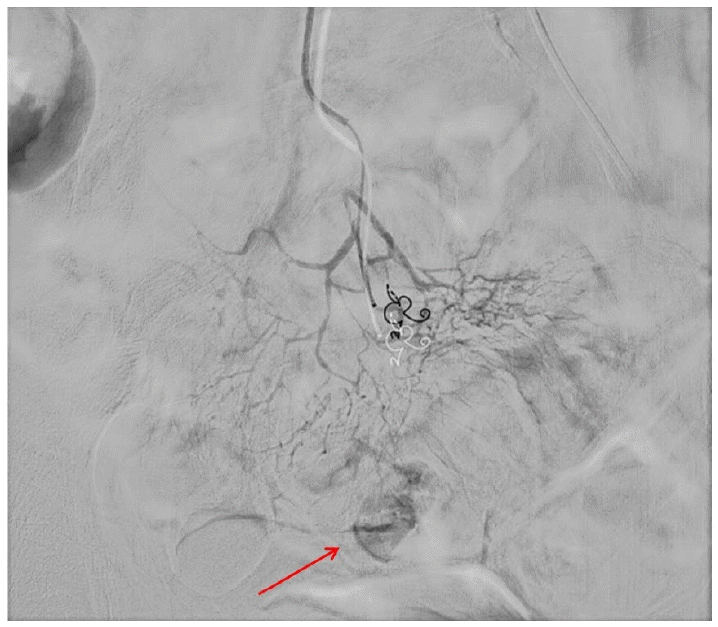

혈관조영술 상에서 회장동맥(Ileal branch)으로부터 혈관 외 유출(extravasation)이 관찰되었고 색전술을 시도하였으나 원발 부위로 의심되는 직혈관(vasa recta)의 굵기가 가늘어 미세 카테터 진입이 실패하였다. 출혈점에 인접하여 최대한 원위부 혈관을 정밀 선택(superselection)한 후 2 mm-3 cm 코일 2개를 사용하여 색전술을 시행하였고(Fig. 2) control digital subtraction angiography 상 에서 혈관 외 유 출이 확인되지 않아 시술을 종료하였다.

Figure 2.

(A) Arrows indicate the ileal branch of the superior mesenteric artery. (B) Embolization microcoil within the ileal arterial branch.